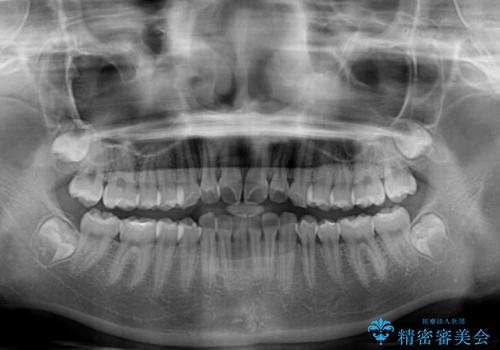

- 上下前歯のねじれを気にして来院された患者様です。

ワイヤー矯正でもマウスピース矯正でも対応可能でしたが、マウスピース矯正の自己管理が面倒であること、上顎前歯の捻転が著しいことから、ワイヤー矯正での治療を希望されました。